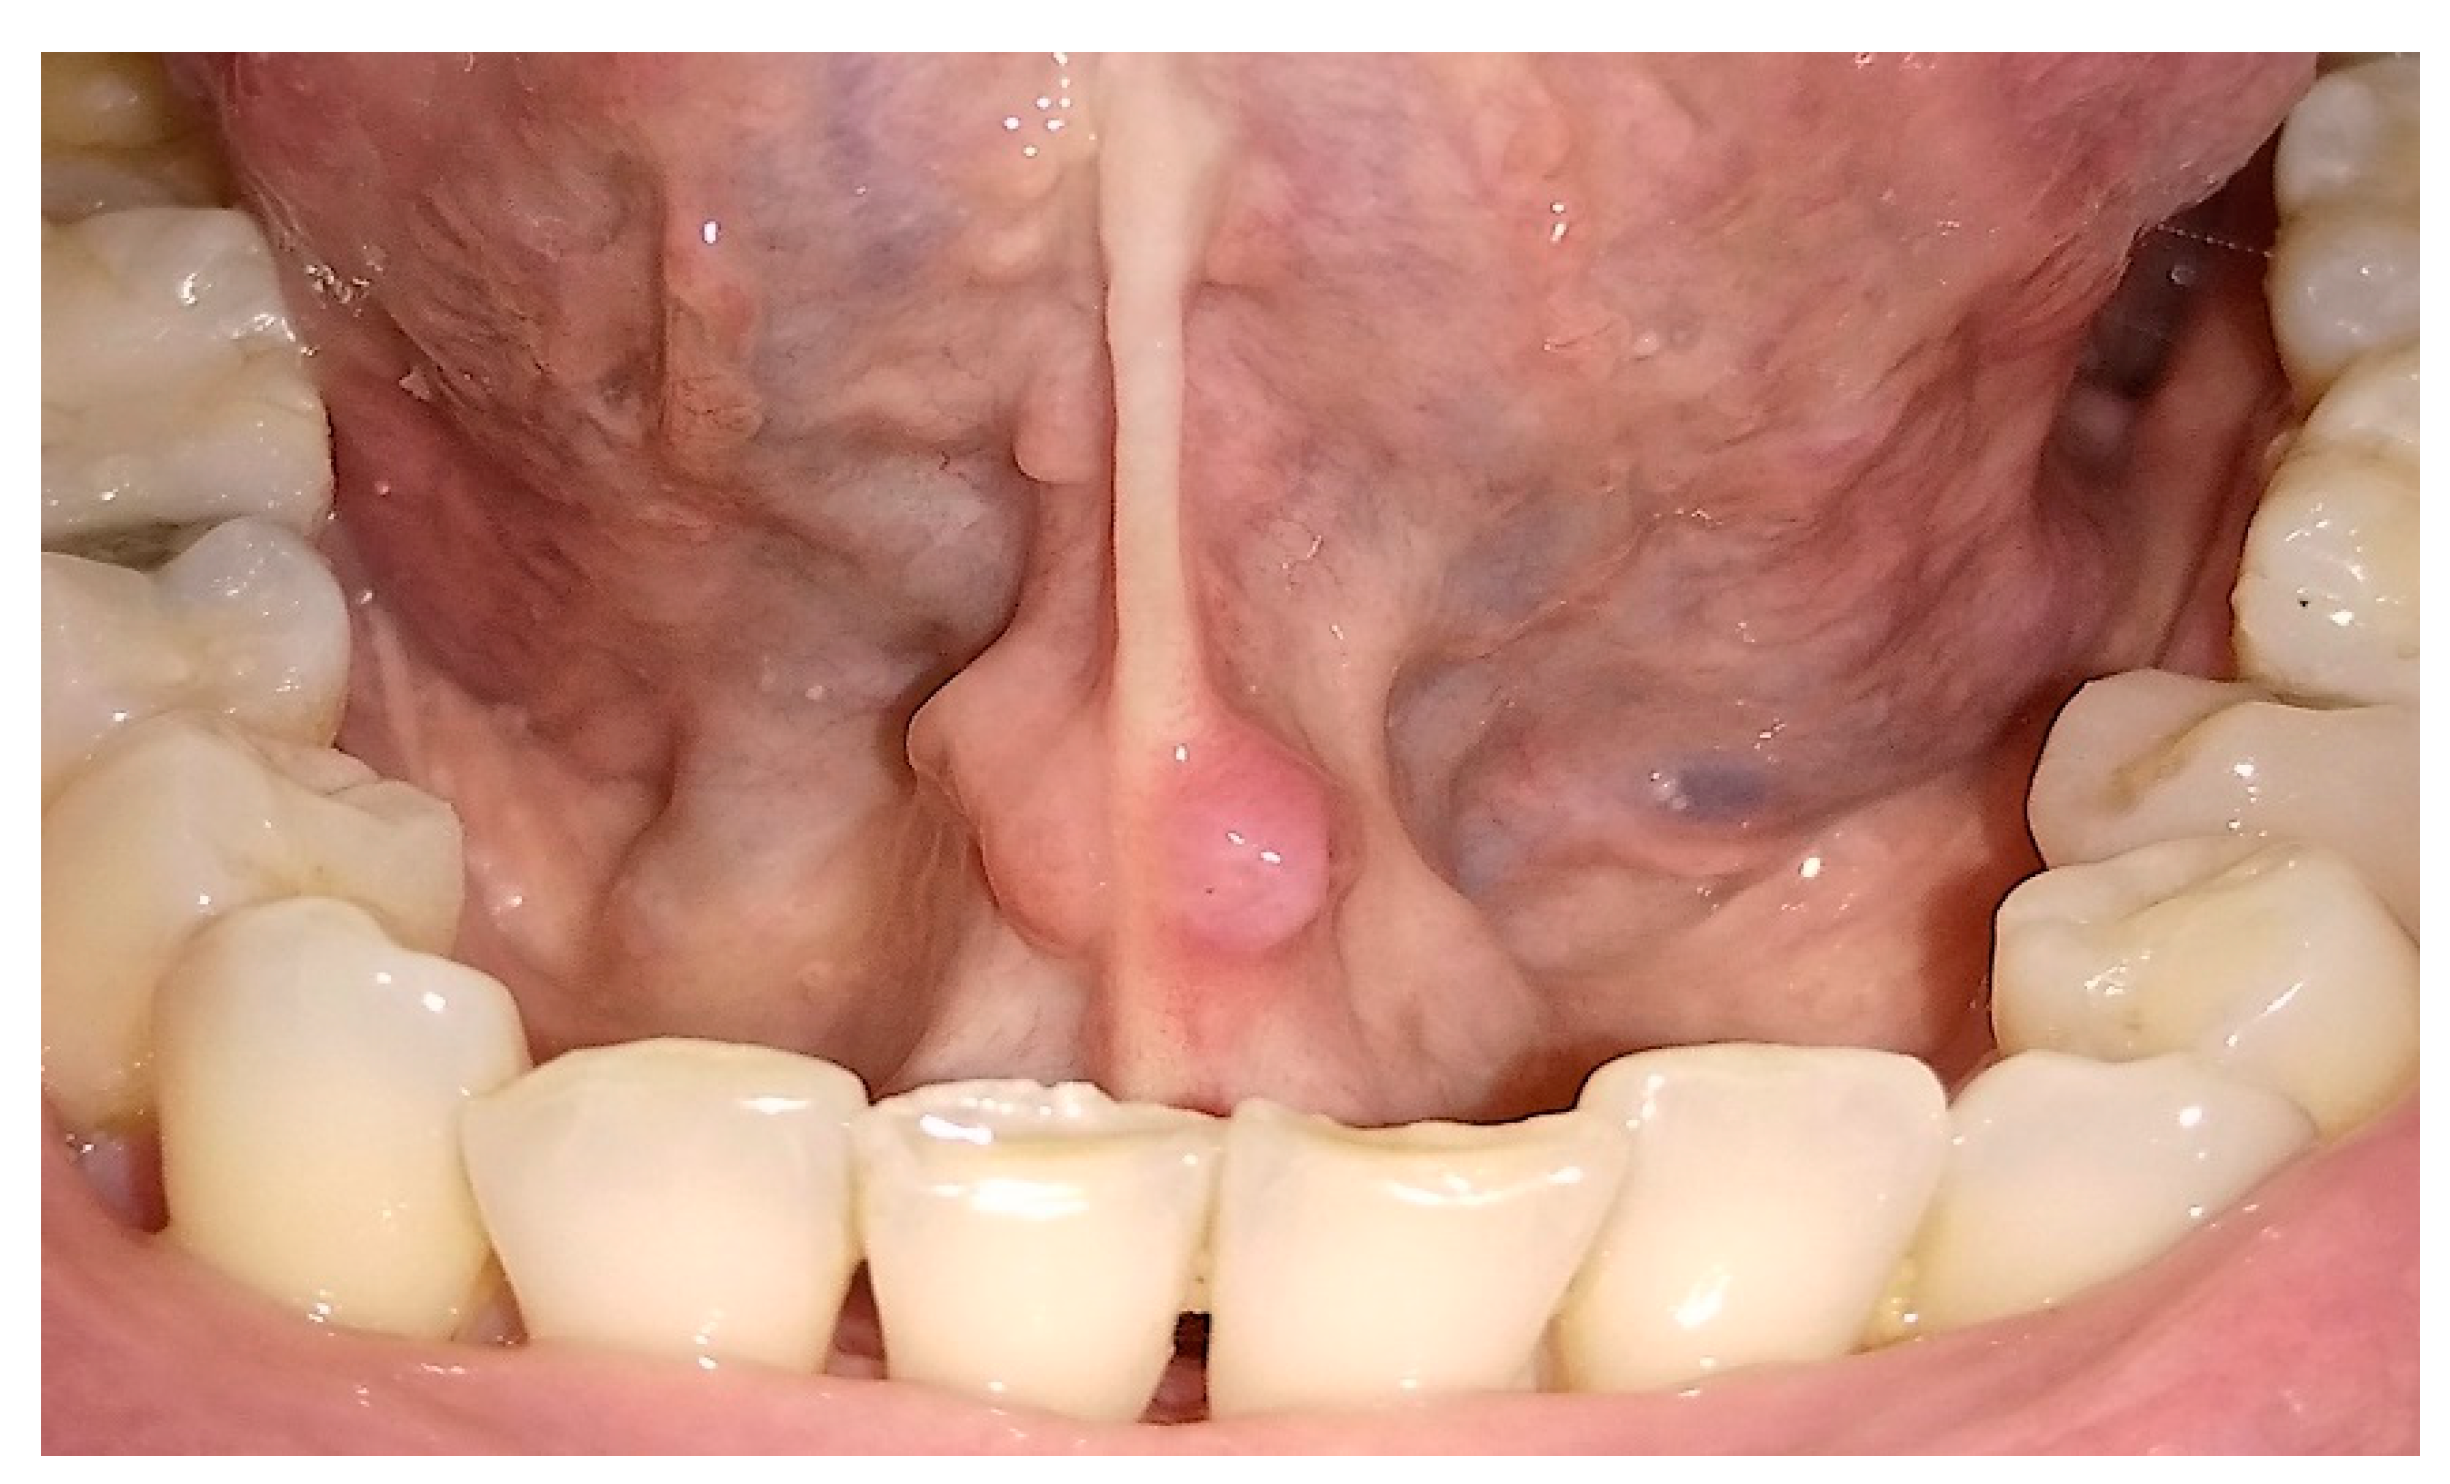

Photobiostimulation Therapy in Non-Responsive Oral Ulcerative Aftosis: 3 Cases Reports †

3. Results